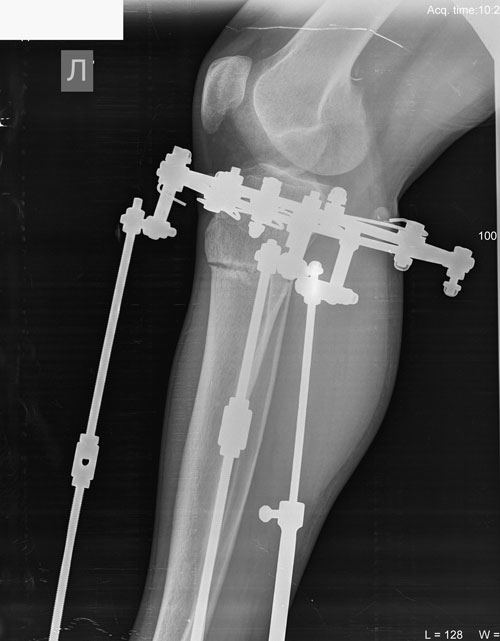

Рентген в 56 дней.

Сращение идёт отлично!

П1.jpg

П2.jpg